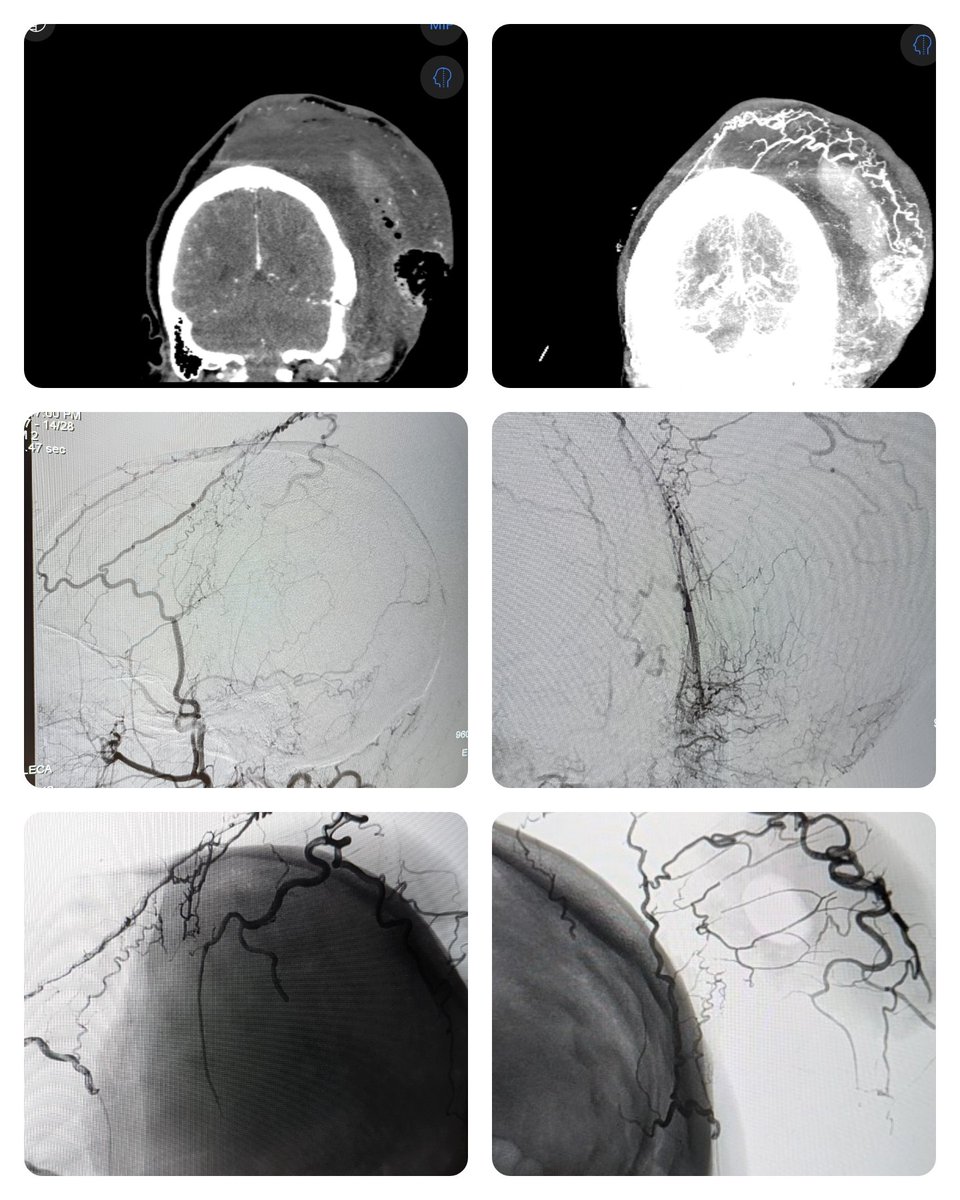

27 yo with neurofibromatosis that's been debulked several times. Involved in a trauma during which she has an intratumor hemorrhage. She got a bedside I&D with 500cc of blood evacuated... and then it wouldn't stop bleeding. So we embolized it.

27 yo with neurofibromatosis that's been debulked several times. Involved in a trauma during which she has an intratumor hemorrhage. She got a bedside I&amp;D with 500cc of blood evacuated... and then it wouldn't stop bleeding.

So we embolized it.